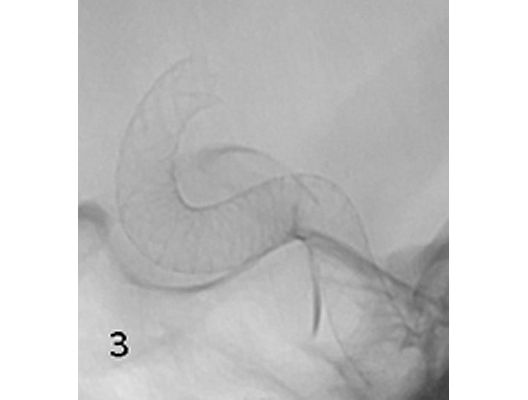

Angiographie: Rekanalisierende Verfahren

Rekanalisierende Verfahren (Wiedereröffnung von Blutgefäßen)

Mit den modernen Verfahren zur Wiedereröffnung von verschlossenen Blutgefäßen können wir Patienten mit Schlaganfall in vielen Fällen helfen. Das folgende Beispiel zeigt die angiographischen Bilder eines Patienten, der mit vollständiger Lähmung der rechten Körperhälfte und einer schweren Sprachstörung eingeliefert wurde. Ursächlich zeigte sich ein Verschluss der linken Halsschlagader, vermutlich auf dem Boden einer arteriosklerotischen Einengung (Bild 1). Das Gefäß wurde daraufhin mit einem Stent wiedereröffnet (Bild 2). Zusätzlich zeigte sich ein Verschluss der Endstrecke des Gefäßes durch Blutgerinnsel (Bild 3). Diese konnten vollständig entfernt werden (Bild 4). Der Patient erholte sich nach der Behandlung innerhalb weniger Tage vollständig.